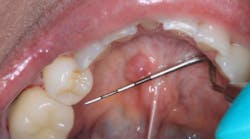

Clinical dental case: Asymptomatic fluid-filled lesions in the vestibular mucosa (nos. 7–10)

Patient presentation: A 17-year-old male patient presented at the initial dental appointment with the following:

Chief complaint: None. The lesions were discovered during a routine oral examination.

Clinical findings:

- Seven asymptomatic, fluid-filled lesions

- Lesions ranged in size from 2 mm to 5 mm

- Lesions similar in color to the surrounding mucosa

- Location: vestibular mucosa, in the region of teeth nos. 7–10

Follow-up appointment: Only three of the original lesions remained.

The presentation of multiple, asymptomatic, fluid-filled lesions on the vestibular mucosa, with a color similar to the surrounding tissue, further supports the likelihood of a mucocele or a mucous retention cyst. The spontaneous resolution of some lesions further strengthens this hypothesis.

Observation: Given the strong clinical suspicion of mucoceles, the spontaneous resolution of some lesions, and the absence of concerning features, continued observation is appropriate. The patient should be instructed to monitor the remaining lesions and report any changes in size, symptoms, or the development of new lesions.

Biopsy and histopathological examination: If the lesions persist, increase in size, or become symptomatic, a biopsy is indicated to confirm the diagnosis and rule out other possibilities.